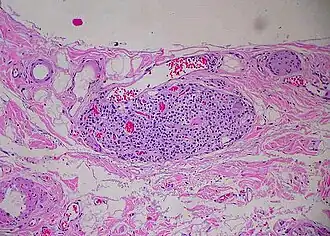

Paraganglion of gallbladder

A paraganglion (pl. paraganglia) is a group of non-neuronal cells derived of the neural crest. They are named for being generally in close proximity to sympathetic ganglia. They are essentially of two types: (1) chromaffin or sympathetic paraganglia made of chromaffin cells and (2) nonchromaffin or parasympathetic paraganglia made of glomus cells. They are neuroendocrine cells, the former with primary endocrine functions and the latter with primary chemoreceptor functions.[1]